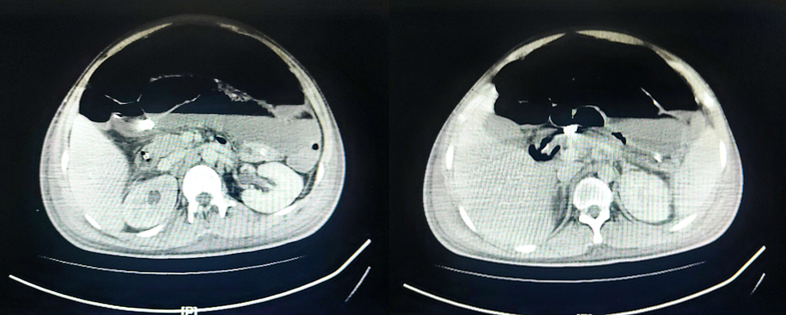

8月25日停用达托霉素,由于当时艾沙康唑暂时不可及,所以使用了两性霉素B胆固醇硫酸酯250 mg/d+亚胺培南抗感染。8月29日腹部MRI平扫+增强+弥散加权成像(DWI):右侧中下腹腔内(以右半结肠为中心)邻近前腹壁-腹膜后巨大边缘环形强化病灶,范围较前稍进展(图7),考虑升结肠缺血坏死,感染较前稍进展,并肠瘘可能。图7 腹部MRI平扫+增强+DWI(2022-08-29)第二次MDT(8月29日):血液科、感染科、普外科、消化科、麻醉科、营养科、临床药学科。MDT意见:患者目前有手术指征,但手术风险极高,预后极差,且费用高昂,继续积极抗感染治疗。患者体温36℃,腹胀腹痛较前稍缓解,可解少量大便,肠梗阻解除,生命体征平稳,转回血液科继续治疗。抗感染:哌拉西林他唑巴坦,两性霉素B胆固醇硫酸酯+艾沙康唑200 mg q8h(第3天开始200 mg qd)。9月2日, 患者体温36.7℃, 全腹胀痛好转, 右下腹皮肤溃烂黑痂, 范围约7 cm×8 cm, 局部破溃渗液(图8)。9月4日晚患者再次出现发热,体温38.3,将哌拉西林他唑巴坦改为亚胺培南+万古霉素抗感染。查血常规:白细胞13.12×109/L,中性粒细胞绝对值11.43×109/L;降钙素原3.57 ng/ml。分泌物细菌(真菌)培养:鲍曼不动杆菌(多重耐药)。9月5日腹部MRI平扫+增强+DWI: 右侧中下腹腔内(以右半结肠为中心)-邻近前腹壁-腹膜后巨大边缘环形强化病灶较前向外膨出、范围较前缩小(图9),考虑升结肠-邻近小肠及腹壁缺血坏死并感染, 肠瘘形成可能, 肠梗阻较前改善。图9 腹部MRI平扫+增强+DWI(2022-09-05)9月9日患者右下腹坏死物膨出,边缘进一步破溃,脱落,暴露腹腔内容物(图10)。在2019年ECMM发布的《毛霉病诊断和管理全球指南》中,指南小组强烈支持,除全身抗真菌治疗外,在可能的情况下,应尽早完成毛霉病的外科治疗。如有需要,应反复行切除或清创术。第三次MDT(9月9日):感染科、普外科、麻醉科、营养科、消化科、烧伤科、ICU、康复科。MDT意见考虑:患者有手术指征,但手术风险极高,需要多学科联合手术同时进行;尽快完善全腹部CT+腹部血管CTA,完善术前高风险谈话及手术/麻醉评估,患者及家属手术意愿强烈可考虑充分术前准备后手术。9月9日腹部CT+腹部血管CTA:肝中动脉瘤;腹主动脉+肠系膜上、下动脉+肾动脉CTA未见异常。9月10日行腹壁坏死组织切除+回肠部分切除+回肠造瘘+肠粘连松解术,术后转ICU观察。术中见:右下腹一13 cm×13 cm坏死腹壁与肠管组织,与周围组织无粘连,予以取出,回盲部、部分乙状结肠、右侧上段输尿管包裹在腹壁坏死组织中(图11)。病理组织活检:骨骼肌及肠壁可见大量真菌菌丝、孢子及细菌菌团,且部分真菌菌丝及孢子似位于脉管内,倾向侵袭性真菌病并广泛播散;见阑尾组织显著急性坏疽性阑尾炎,阑尾管壁及管腔内见真菌菌丝及孢子。9月14日患者生命体征平稳,无发热,为求坏死腹壁修复,转入烧伤科继续治疗。9月15日患者生命体征平稳,胆仍有腹痛、腹胀,转入胃肠外科治疗,后续进食半流质,腹痛缓解,造瘘处有排便排气。术后持续予以两性霉素B胆固醇硫酸酯+艾沙康唑治疗。9月20日腹部增强CT示(图12):“腹壁坏死组织切除+回肠部分切除+回肠造瘘+肠粘连松解术”术后改变,右中下腹术区少量渗出、积液;左侧回肠造瘘口近端小肠积液、积气扩张;右侧输尿管上段继发右肾及输尿管上端轻度积水同前;盆腹腔脓肿较前吸收。肠腔内高密度影,造影剂残留?肝中动脉动脉瘤较前增大。肝脏多发低密度灶同前,仍考虑小脓肿形成可能。9月22日,患者生命体征平稳,复查骨髓形态及流式均未见异常细胞。11月1日,烧伤整形科于全麻下行"右腹壁腹膜补片修补+腹壁缺损右股前外侧皮瓣转移修复术"。术前已停用两性霉素B,予以艾沙康唑口服维持治疗。2024年1月3日随访腹部CT提示患者恢复较好(图13)。